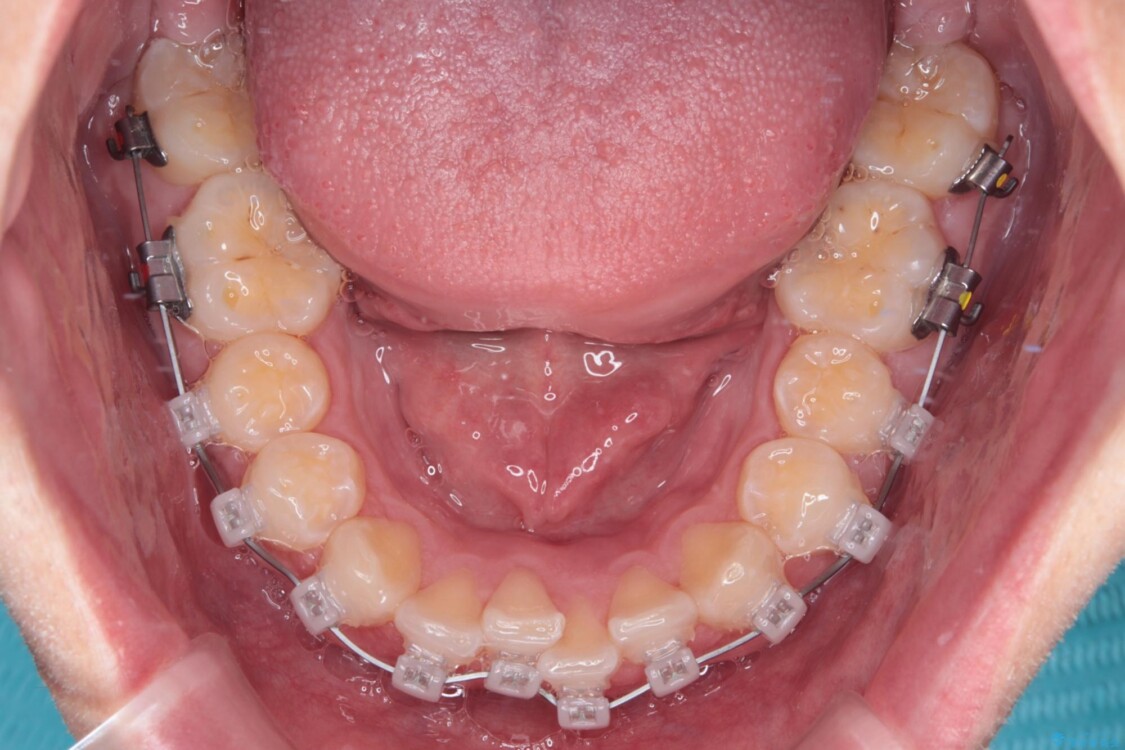

治療途中

• 前歯のガタガタ・奥歯のかみ合わせ(シザーズバイト)を改善|1年半で完了したメタルブラケット矯正 治療途中画像

・費用と期間を抑えるために、多少目立っても効率の良いメタルブラケットを使用

・奥歯のシザーズバイト改善には、口蓋側にアンカースクリュー(TAD)を設置し、矯正用ゴムで内側に牽引

・捻転した第二小臼歯は、ワイヤーと矯正用ゴムの力を用いて正しい位置へ回転移動